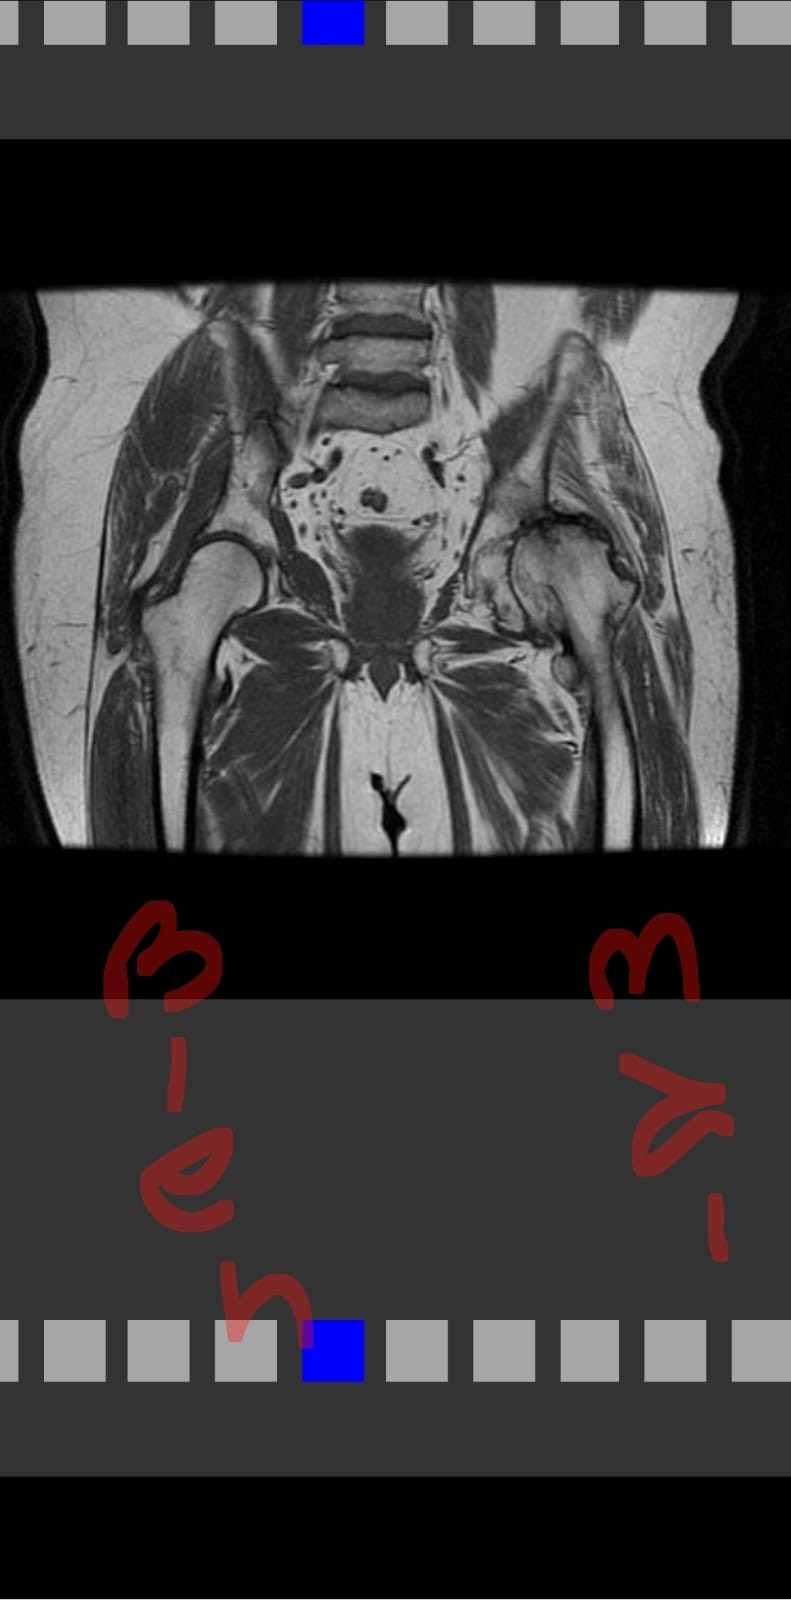

«Mi historia comienza cuando me afilié a la prepaga Crystal Medicina Privada, pagando puntualmente la cuota todos los meses. Mi médico y yo decidimos que necesitaba una operación, pero para realizarla, requería la autorización de la prepaga. En marzo, presenté todos los papeles y estudios necesarios, incluyendo la resonancia magnética nuclear.